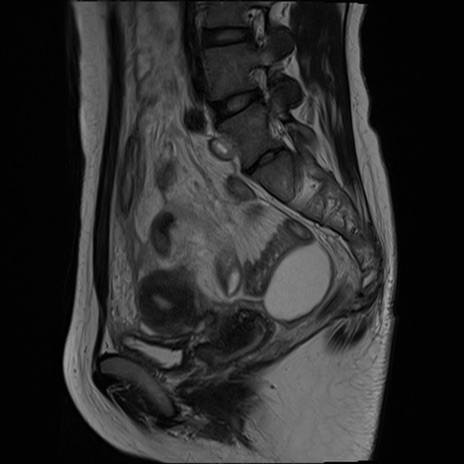

症例39 T2WI(矢状断像)

MRI(4日後)